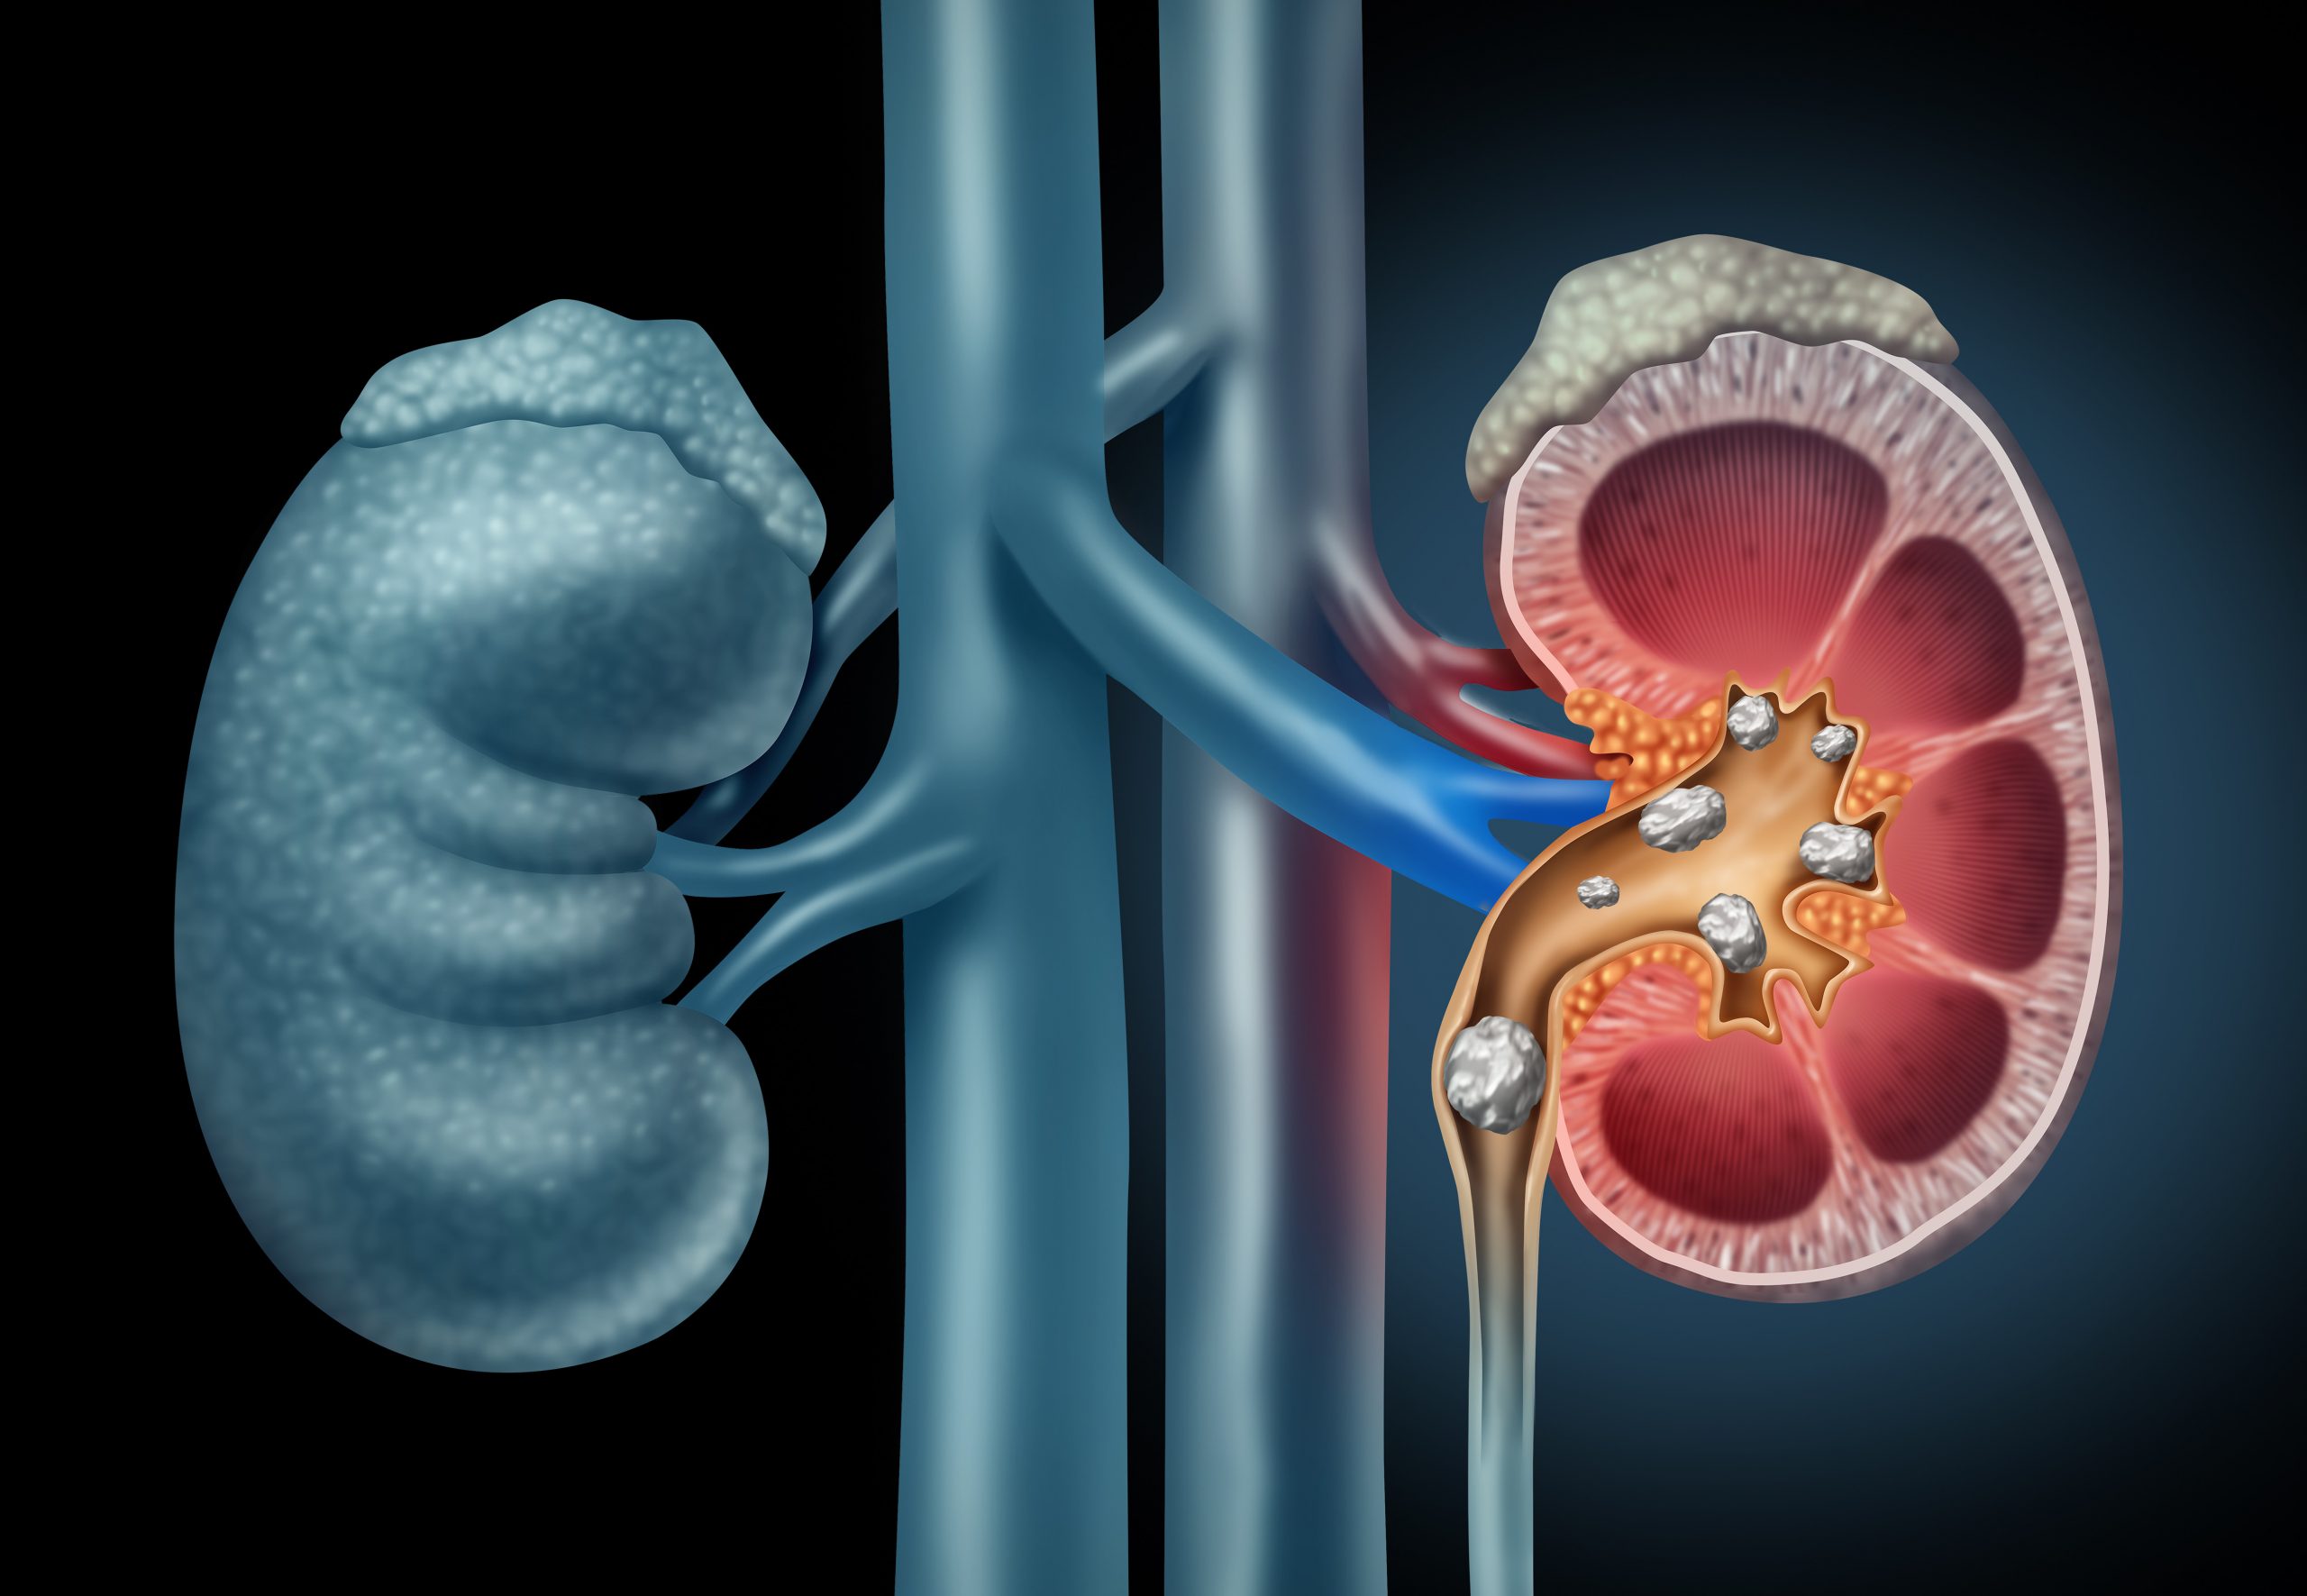

Kidney Stone Management

Expert diagnosis and treatment of kidney stones using minimally invasive techniques such as lithotripsy, ureteroscopy, and percutaneous nephrolithotomy.